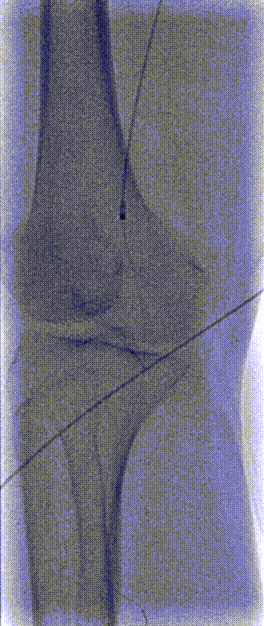

3. 将导丝更换为Rotarex血栓切除系统导丝,退出MPA1导管,沿导丝导入Rotarex血栓切除导管并连接系统,于腘动脉行血栓旋切抽吸。

4.抽吸后造影见:腘动脉血流恢复,管腔局部可见狭窄,沿导丝导入球囊扩张导管(4*200mm,巴德,6atm,3min)于腘动脉病变内分段扩张。扩张后造影见:右股腘动脉至胫前动脉远端血流恢复。